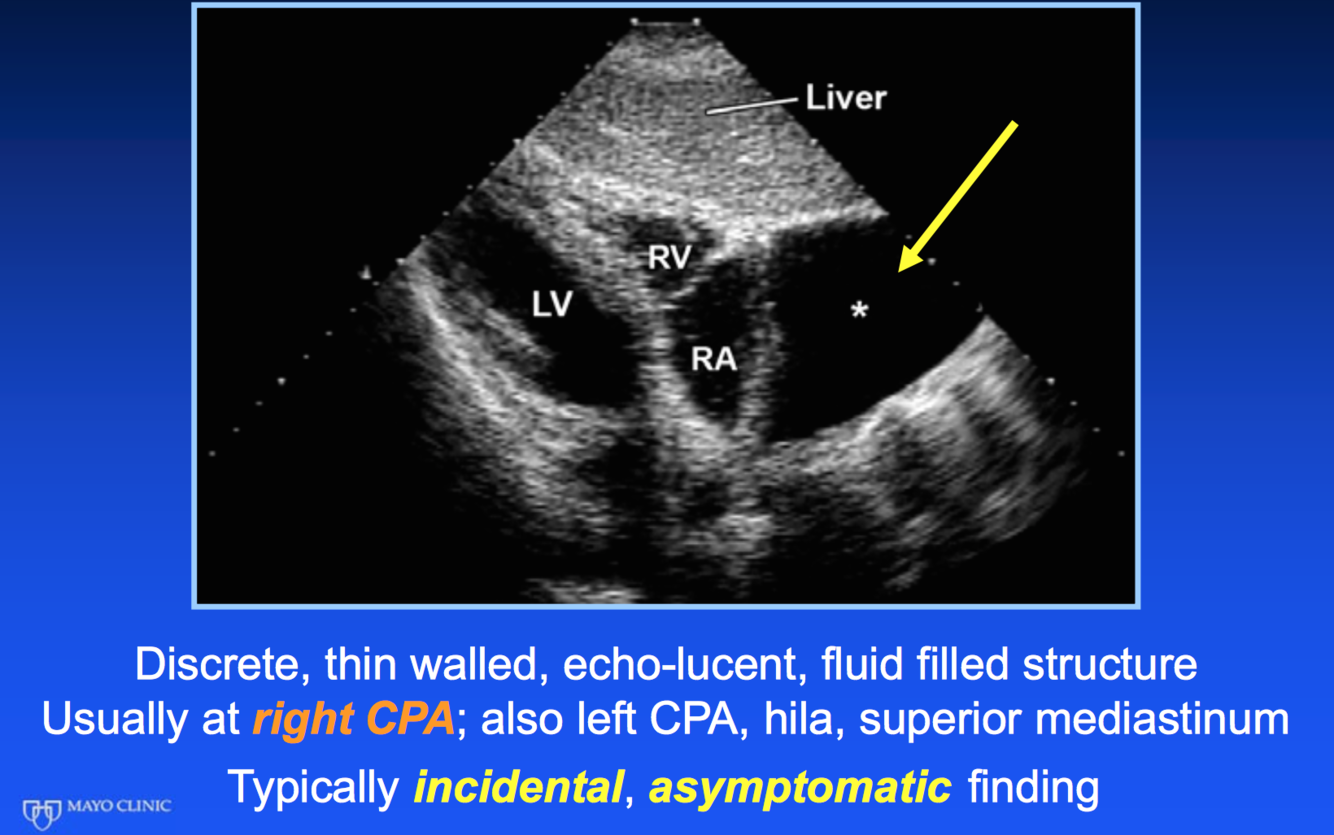

Dx?

pericardial cyst